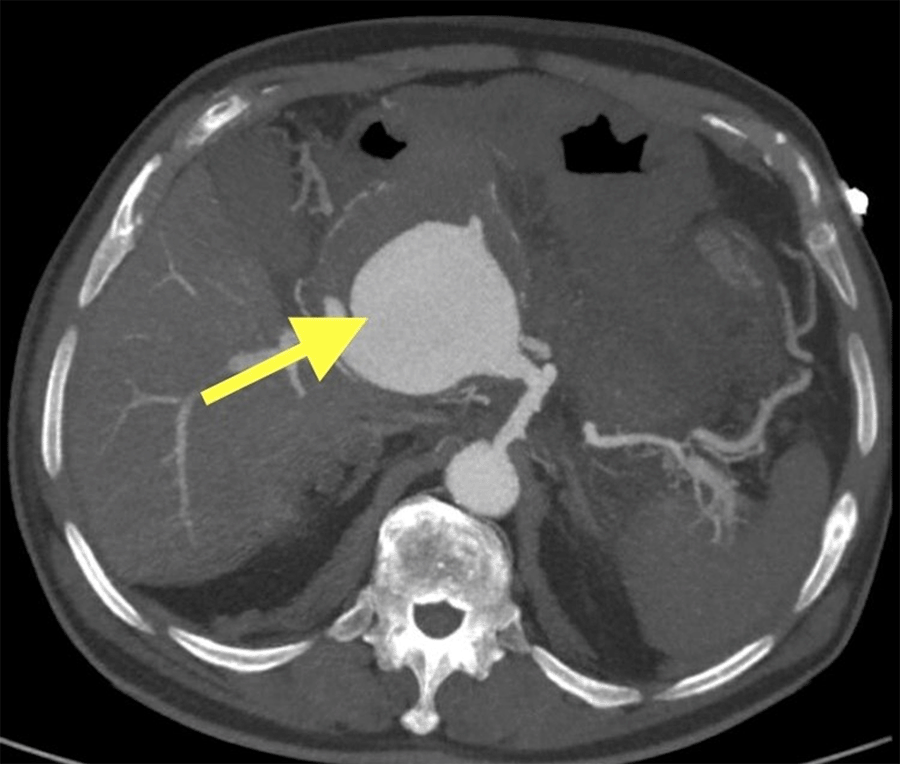

After induction of anesthesia, the patient was prepped and draped in the usual sterile fashion. A midline incision from the xiphoid to the pubic tubercle was performed. The falciform ligament and left triangular ligament of the liver were taken down; next, a Cattel–Braasch maneuver was performed to mobilize the colon and the small bowel. The lesser sac was opened using an energy device, and the distal stomach was stapled off because the pancreas was fused to it. Once the pancreas was identified, we traveled along its inferior border, tied off the splenic vein, and identified the superior mesenteric vein (SMV) and portal vein confluence. The anterior wall of the portal vein was almost entirely fused to the aneurysm, and we were unable to create an appropriate retro-pancreatic tunnel. The hepatic artery was ligated, as well as the common bile duct, to gain access and control over the PV. The gastroduodenal artery was identified and preserved. Once proximal and distal control was obtained, an anterior longitudinal cut into the aneurysm sac was made, the anterior wall was removed, and a large burden of clot was evacuated. At this point, we discovered that the anterior wall of the PV was almost entirely compromised. We decided to use a piece of 15 × 20 cm bovine pericardium as a conduit. We tabularized it with 6-0 Prolene stitches in a running fashion. Proximal and distal control was obtained, and the graft was sewed end-to-end in a single layer running fashion to the SMV on the proximal side and the portal vein stump in the same style on the distal side. Once this was completed, we reperfused and ensured we had good graft flow with Doppler. We desufflated the endovascular balloon but encountered bleeding at the celiac origin. Because the pseudoaneurysm created a significant mass effect distorting the patient's abdominal anatomy significantly, we decided to leave the endovascular balloon insufflated at the celiac trunk origin. We opted to pack the abdominal cavity, leave the abdomen open and transfer the patient to the intensive care unit where he could be resuscitated to take him back to the OR for a second look laparotomy and reconnect the gastrointestinal tract when hemodynamically stable. Before exiting the operating room, a cholecystectomy was performed. The patient was transferred to the intensive care unit, where he was resuscitated and remained intubated.

Figure 2. Portal Vein-Graft With Bovine Pericardium. Published With Permission